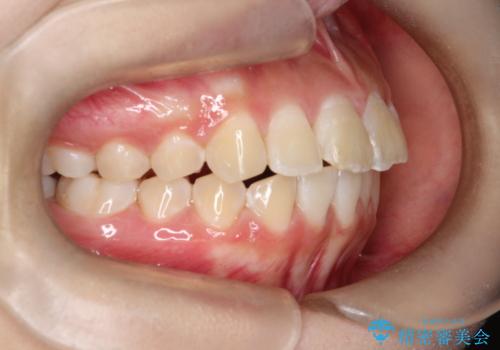

- 前歯が出ていることを主訴に来院されました。

インビザラインにて奥歯の遠心移動を行いながら最大限前歯が下がるように治療を行いました。

今回は遠心移動とIPRによってここまで前歯を下げることができました。